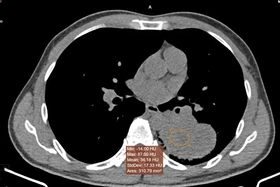

Sau một tháng ho khan, nam bệnh nhân có tiền sử 30 năm hút thuốc lá đến viện trong tình trạng đau đầu, chóng mặt, tê tay và được phát hiện mắc ung thư phổi di căn não.